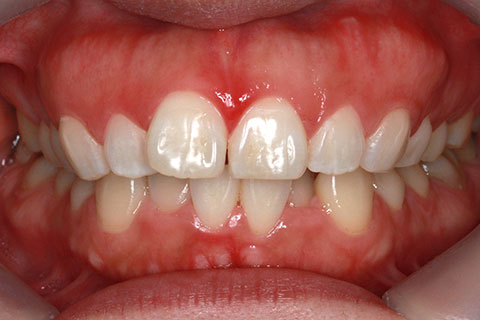

ハーフリンガル矯正3:上の歯のみ舌側矯正で治療(矯正期間24ヶ月)

治療前

治療中(開始直後)

治療中(開始半年後)

治療後

- 年齢・性別

- 25歳女性

- 治療期間

- 2年0ヶ月

- 抜歯

- 上下4番抜歯

- 治療費

- 110万円

- 治療内容

- 施術の副作用(リスク)

- 表側矯正と比較して、力学的な操作性が複雑なため、ボーイングエフェクトを起こしやすい。